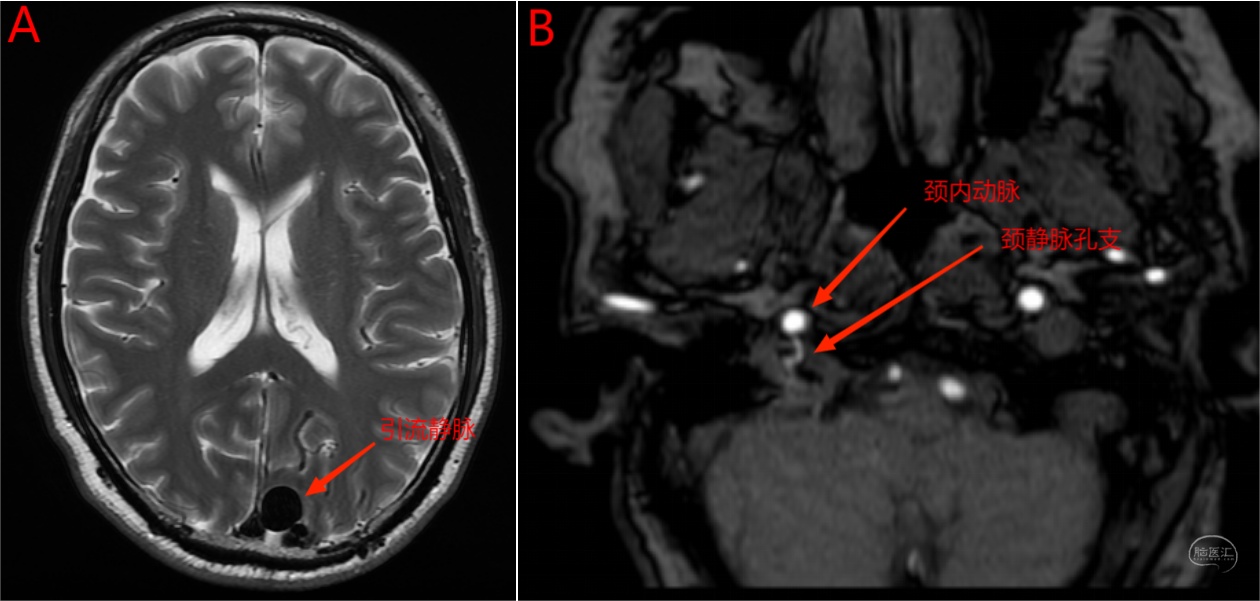

左侧枕部硬脑膜动静脉瘘(Cognard IV级),咽升动脉神经脑膜支(颈静脉孔支)及脑膜中动脉为主要供血动脉,经枕叶皮层静脉引流伴局部瘤样扩张。

图23 颅脑MRI轴位T2像(A)显示左枕叶多发血管流空影伴瘤样扩张,TOF MRA显示颈静脉孔支位于颈内动脉后方并进入颈静脉孔。